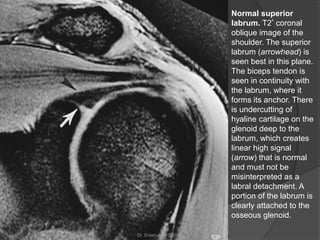

Normal superior

labrum. T2* coronal

oblique image of the

shoulder. The superior

labrum (arrowhead) is

seen best in this plane.

The biceps tendon is

seen in continuity with

the labrum, where it

forms its anchor. There

is undercutting of

hyaline cartilage on the

glenoid deep to the

labrum, which creates

linear high signal

(arrow) that is normal

and must not be

misinterpreted as a

labral detachment. A

portion of the labrum is

clearly attached to the

osseous glenoid.